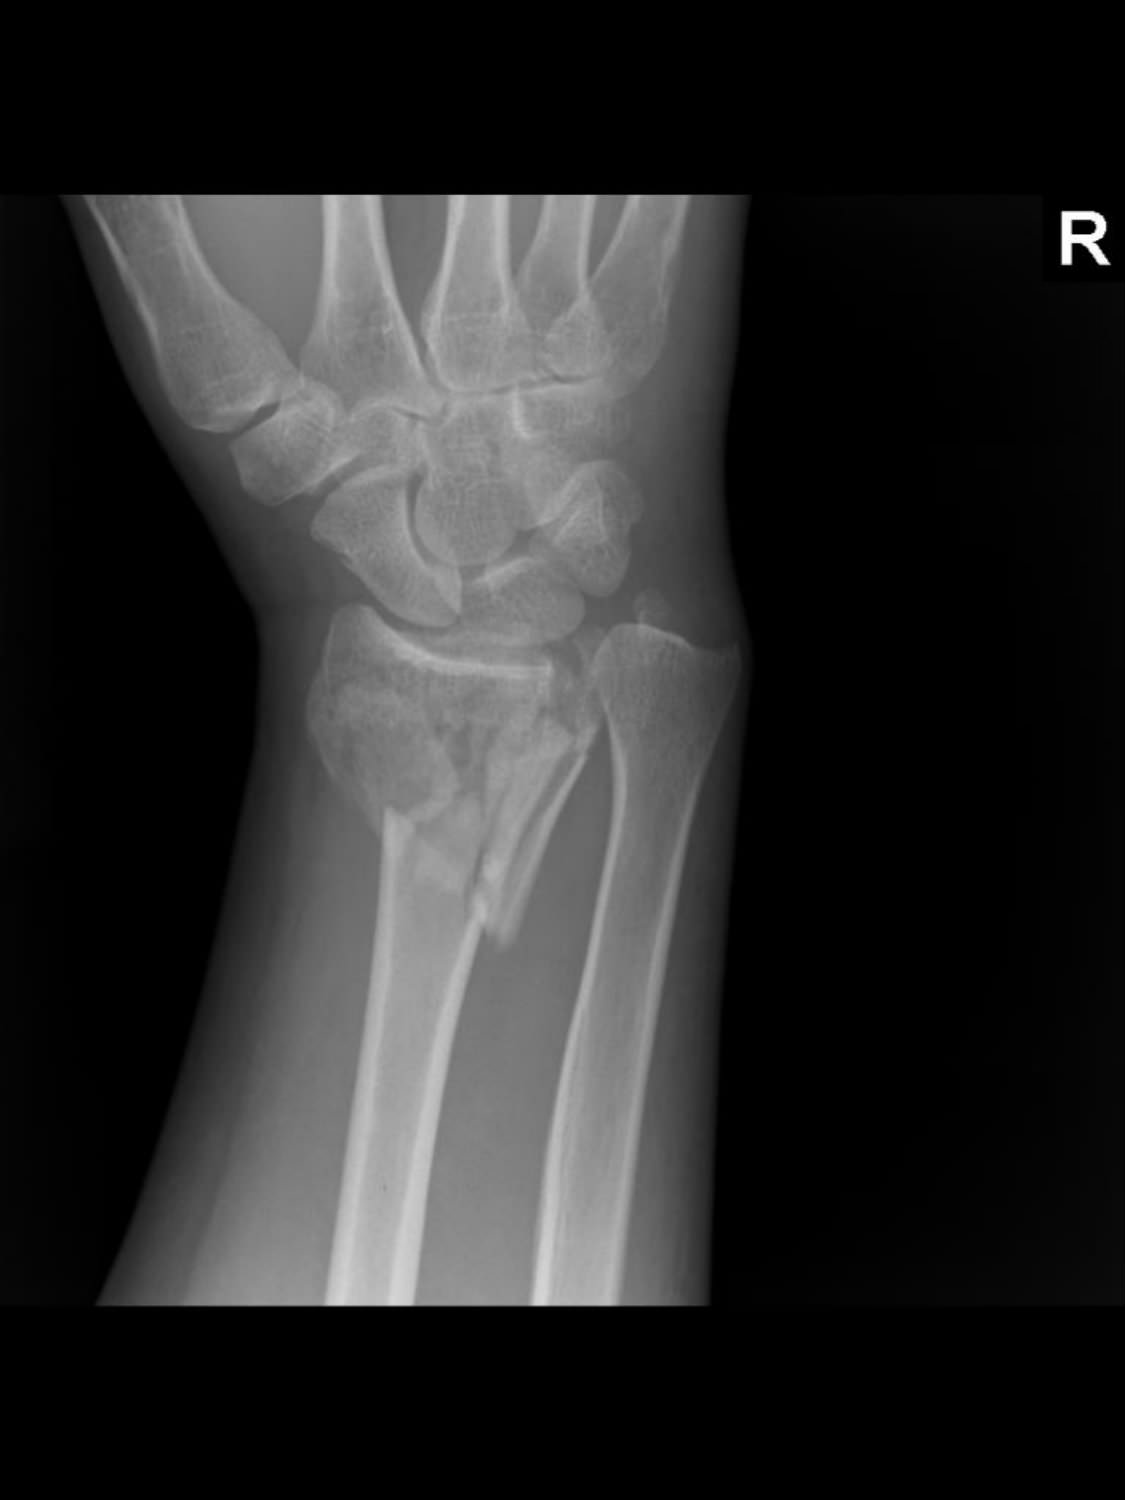

JL is a gifted toymaker by profession, nearly ending his career after a fall from a ladder shattered both wrists. Simultaneous volar plate fixation via open surgery to wrists was performed allowing him to go back to his trade. One was so complex that a revision surgery was needed some weeks later. However, JL went on to not only regain full use of his hands, as seen here, but he embarked on a fitness program and got in much better shape than he was in before. Despite titanium plates in both wrists, he can now do more pushups and bench press much more weight than before the surgery. This indicates that even with a complex injury, a motivated patient can get back to normal if the initial surgery is correctly done. The importance of a specialist cannot be underestimated.